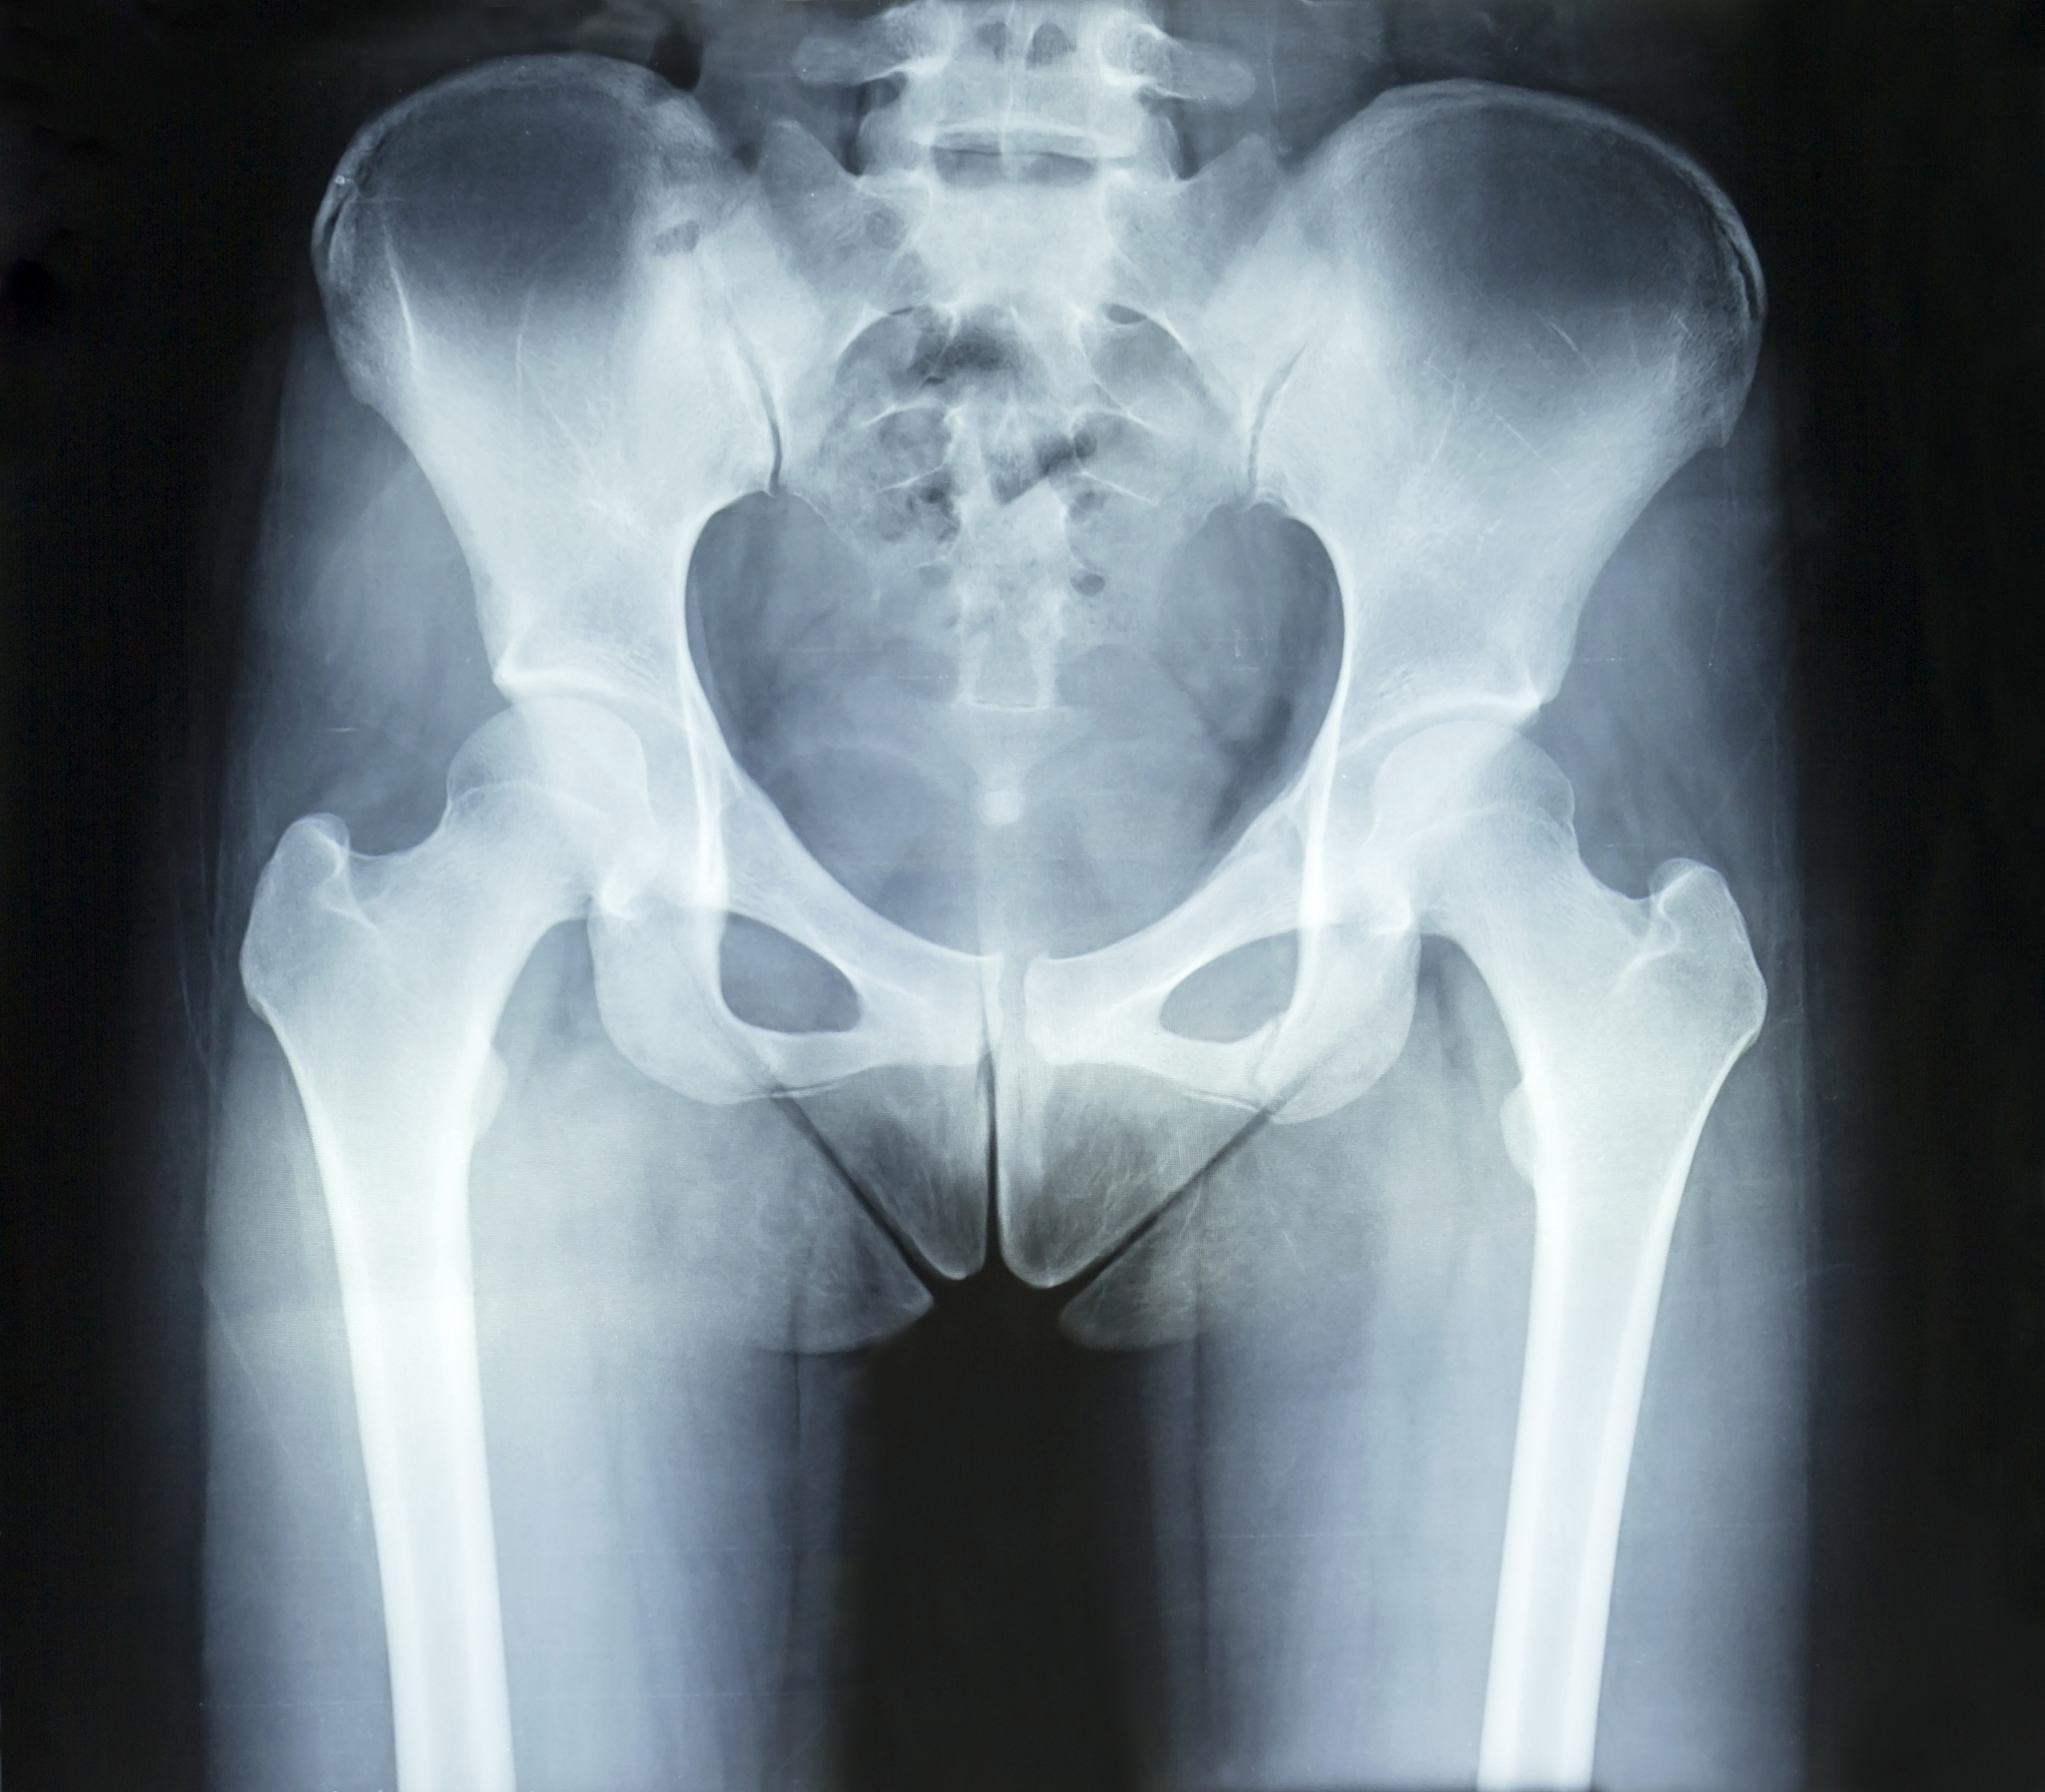

骨盆骨折合并失血性休克手术:C臂X光透视的应用

骨盆骨折合并失血性休克手术中,不断使用C臂X光透视,可以实时观察骨折复位情况和钢板螺钉置入情况,以确定手术治疗效果。C臂X光透视能够提供清晰的影像,帮助医生准确判断骨折部位和程度,并指导手术操作。同时,它还能实时监控钢板螺钉的置入位置和固定效果,确保手术的成功率。